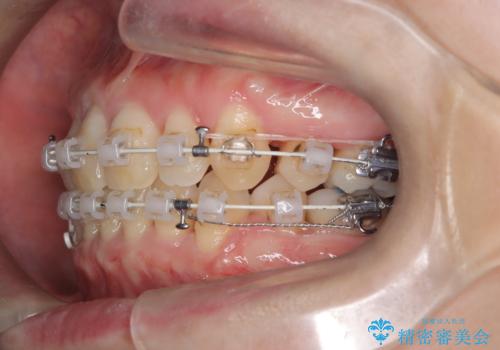

- 前歯の凸凹と前突感を改善するため、上下左右の4番を抜歯し、空いたスペースを利用して前歯を後方へ下げる審美ワイヤー矯正を計画しました。抜歯後は透明で目立ちにくい審美ブラケットを装着し、ワイヤーを用いて徐々に歯列を整えます。毎月1回の調整を通じて歯並びの変化を確認しながら、丁寧に矯正を進め、約2年で理想的な歯列と噛み合わせを完成させることを目指します。

前歯が前に出ていることや歯並びの凸凹が気になるという主訴でした。十分なスペースを確保するため上下左右の第一小臼歯(4番)を抜歯し、そこに前歯を移動させて整列を行いました。矯正装置には目立ちにくい透明なブラケットを選択し、見た目のストレスを軽減。矯正期間中は定期的な通院でワイヤーを微調整し、無理なく確実に歯を動かしました。治療後は前歯が自然な位置に下がり、口元の突出感が解消されるとともに、美しく整った口元に仕上がり、患者様にも大変喜んでいただけました。